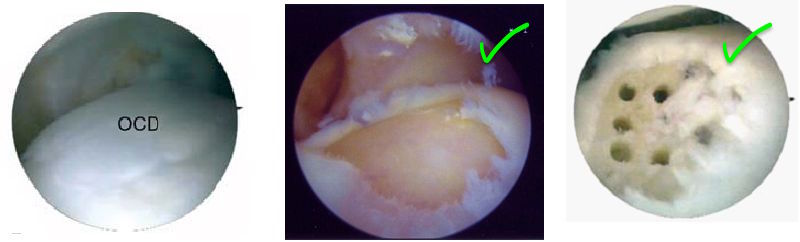

Why are we so confident in our instruments?

- Made in the USA

- Sterilized in the USA

- Patented drill geometry, curved drill shaft, & steerable guide system

- Proven faster procedure times

- No metallic debris due to proprietary alloy composition (materials developed for the

SR-71 aircraft and by NASA for the space shuttle)

- Easier to use with increased consistency between surgeons

- Reduced trauma and recovery times for the patient

Don’t use K-wires (which create bone fragments) or awls (which slip and cause peripheral damage) for drilling or microfracture procedures.

Use Precision Arthroscopic shavers, burrs, and drills for precise, controlled remodeling.